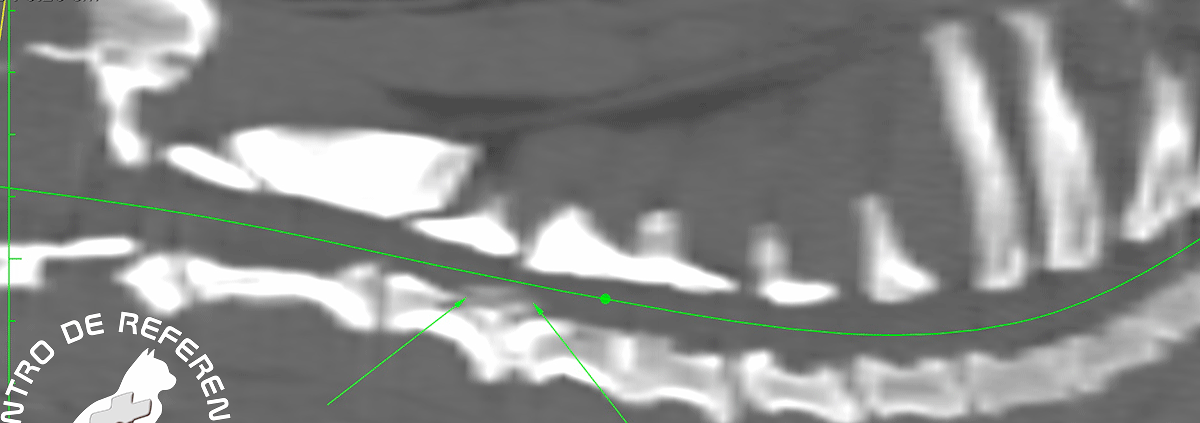

Tomografía computarizada. Se observa una hernia discal calcificada, migrada, central, sin lateralización aparente.

La tomografía computerizada (TAC)se utiliza para revelar el alcance del daño producido por la hernia discal y ayudar a planificar la cirugía. En casos muy leves de hernia discal, se puede intentar el tratamiento médico con relajantes musculares, analgésicos o esteroides orales. Aunque esto a menudo falla.